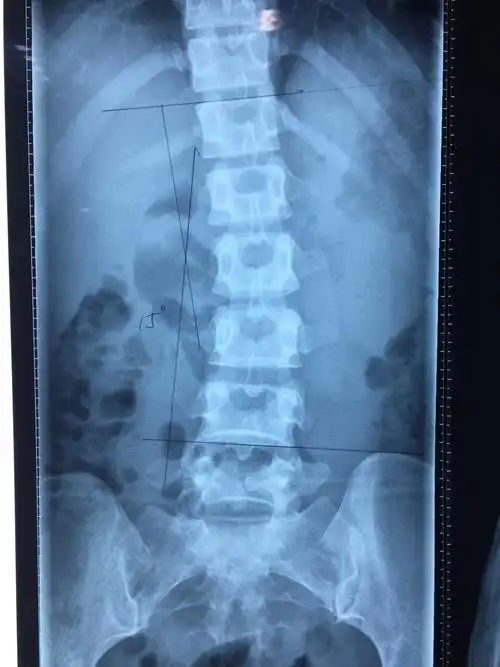

典型腰椎间盘脱出病例的脊柱侧路镜微创手术病例

患者术前:腰椎侧位x线片